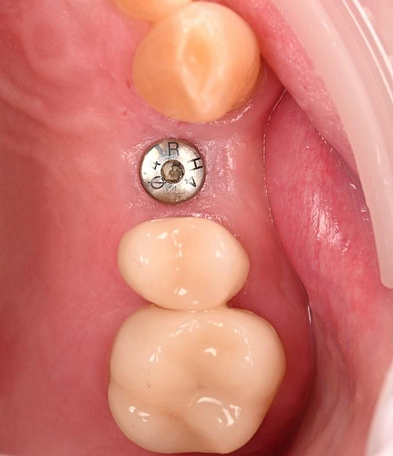

The Osstem OneGuide kit is used with a fully guided osteotomy and implant placement.

Osstem TSIII D4 x H10mm implant on NoMount driver.